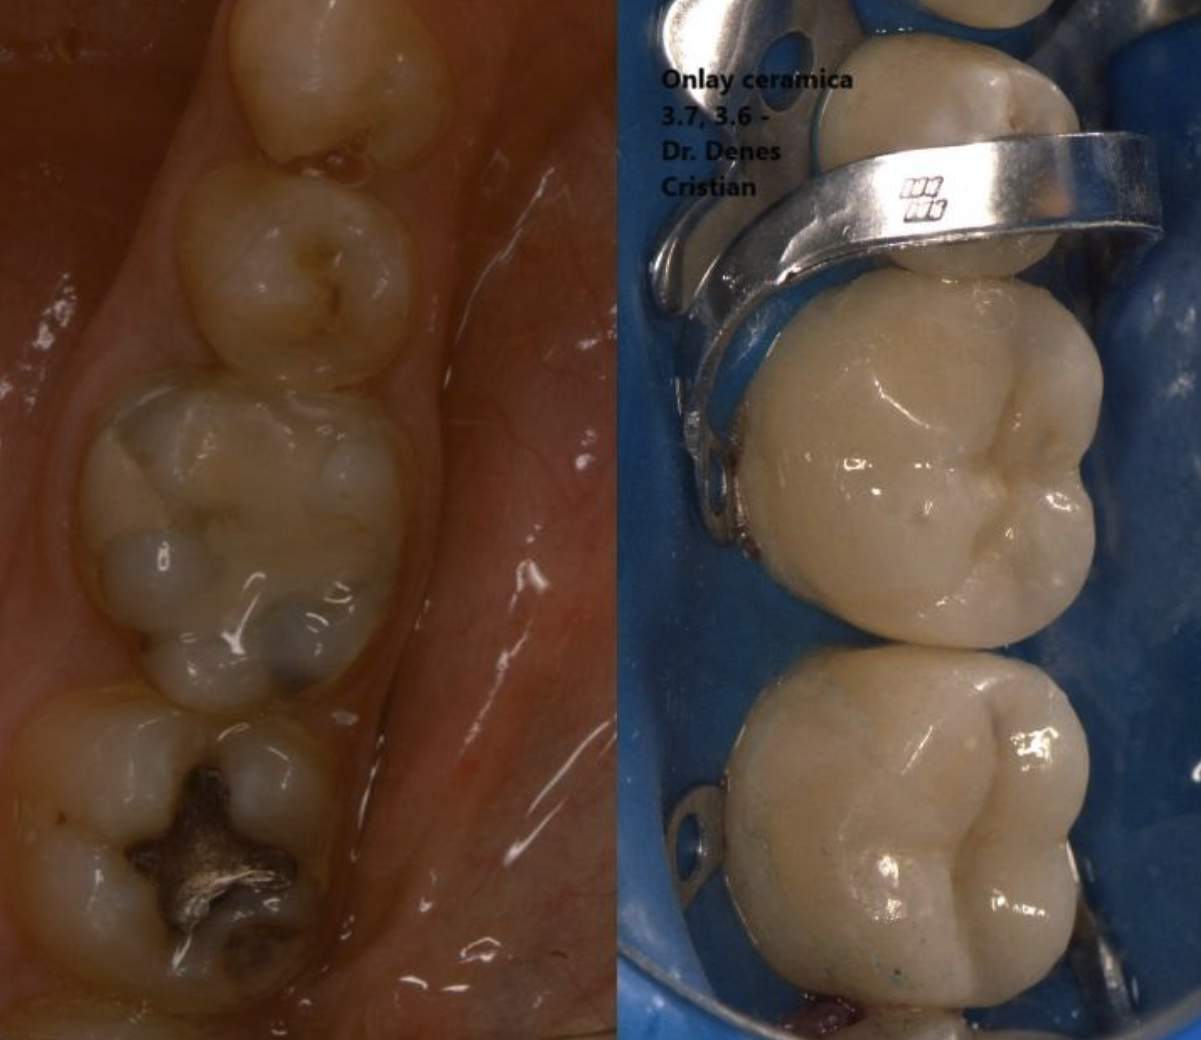

Figura 6. Aspectul înainte și după al dinților tratați prin coroane parțiale ceramice